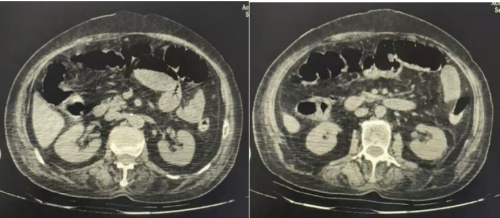

胸+全腹部CT: